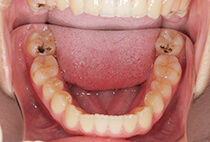

治療前

治療後

八重歯の見た目が気になってご来院されましたが、実は顎の痛みや開口障害など、顎関節症の症状もありました。

そのため、かみ合わせと顎関節症の治療を同時に行ったにもかかわらず、2年間で治療が終了。

かみ合わせが整い咬筋の過緊張も改善しました。咬筋の肥大も治ってフェイスラインがすっきりしました。

最終的には美しい歯並びと、安定した痛みのないかみ合わせが実現しました。

しっかり前歯を下げるために、インプラントアンカーを使用してコントロールしました。

かみ合わせが整うと咬筋の過緊張が改善。

過緊張による筋肉肥大も改善しフェイスラインもすっきりしました。